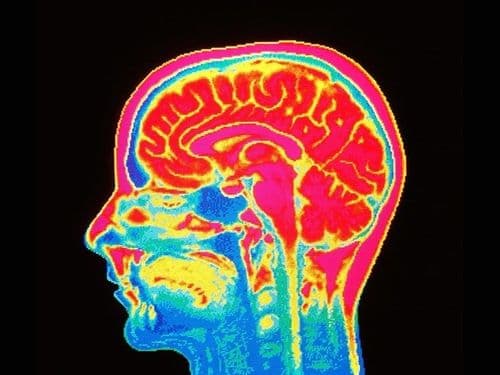

डिप्रेशन समजून घेऊया... डिप्रेशनला तुमच्या मेंदूतली ही रसायनं कारणीभूत आहेत!!

तुम्हांला हे तर माहित आहेच की आपल्या भावभावना हा सगळा केमिकल लोचा असतो. साहजिकच माणूस डिप्रेस असण्यामागे मेंदूमधल्या केमिकल्सचा मोठा हात असतो. वेगवेगळी केमिकल्स वेगवेगळ्या प्रकारे परिणाम करतात. आज आम्ही बोभाटाच्या वाचकांसाठी डिप्रेशनसाठी कारणीभूत असणाऱ्या काही महत्त्वाच्या केमिकल्सबद्दल आणि त्यांच्या मेंदूवर होणाऱ्या परिणामांबद्दल बोलणार आहोत.

माणसला नैराश्य जाणवू देणारी मुख्य केमिकल्स आहेत- डोपामाईन, सेरेटोनिन, नोरापिनेफ्रिन. चला जाणून घेऊयात यांचा आपल्या मेंदूवर नक्की कसा आण काय परिणाम होतो.